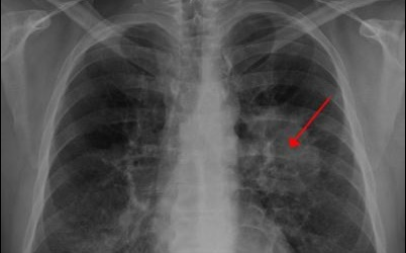

6. 폐암 초기 증상 - 혈담

혈전은 반드시 폐암이 아니어도 나타날 수 있습니다 . 혈담이란 기침 후에 피가 나오 거나 가래에 피가 섞여 있는 것을 혈담 이라고 합니다 . 그러나, 의심스러운 폐암의 초기 증상의 혈담은, 선홍색의 비교적 선명한 피가 나오는 것을 의심해 봐야 합니다 . 이것은 암세포 때문에 폐가 괴사하기 때문 입니다 . 이 경우 폐암 초기보다는 암세포가 확장되었다고 보는 것이 좋습니다 . 폐암 환자의 25% 가 혈담을 했다고 통계가 나온 적이 있습니다 .